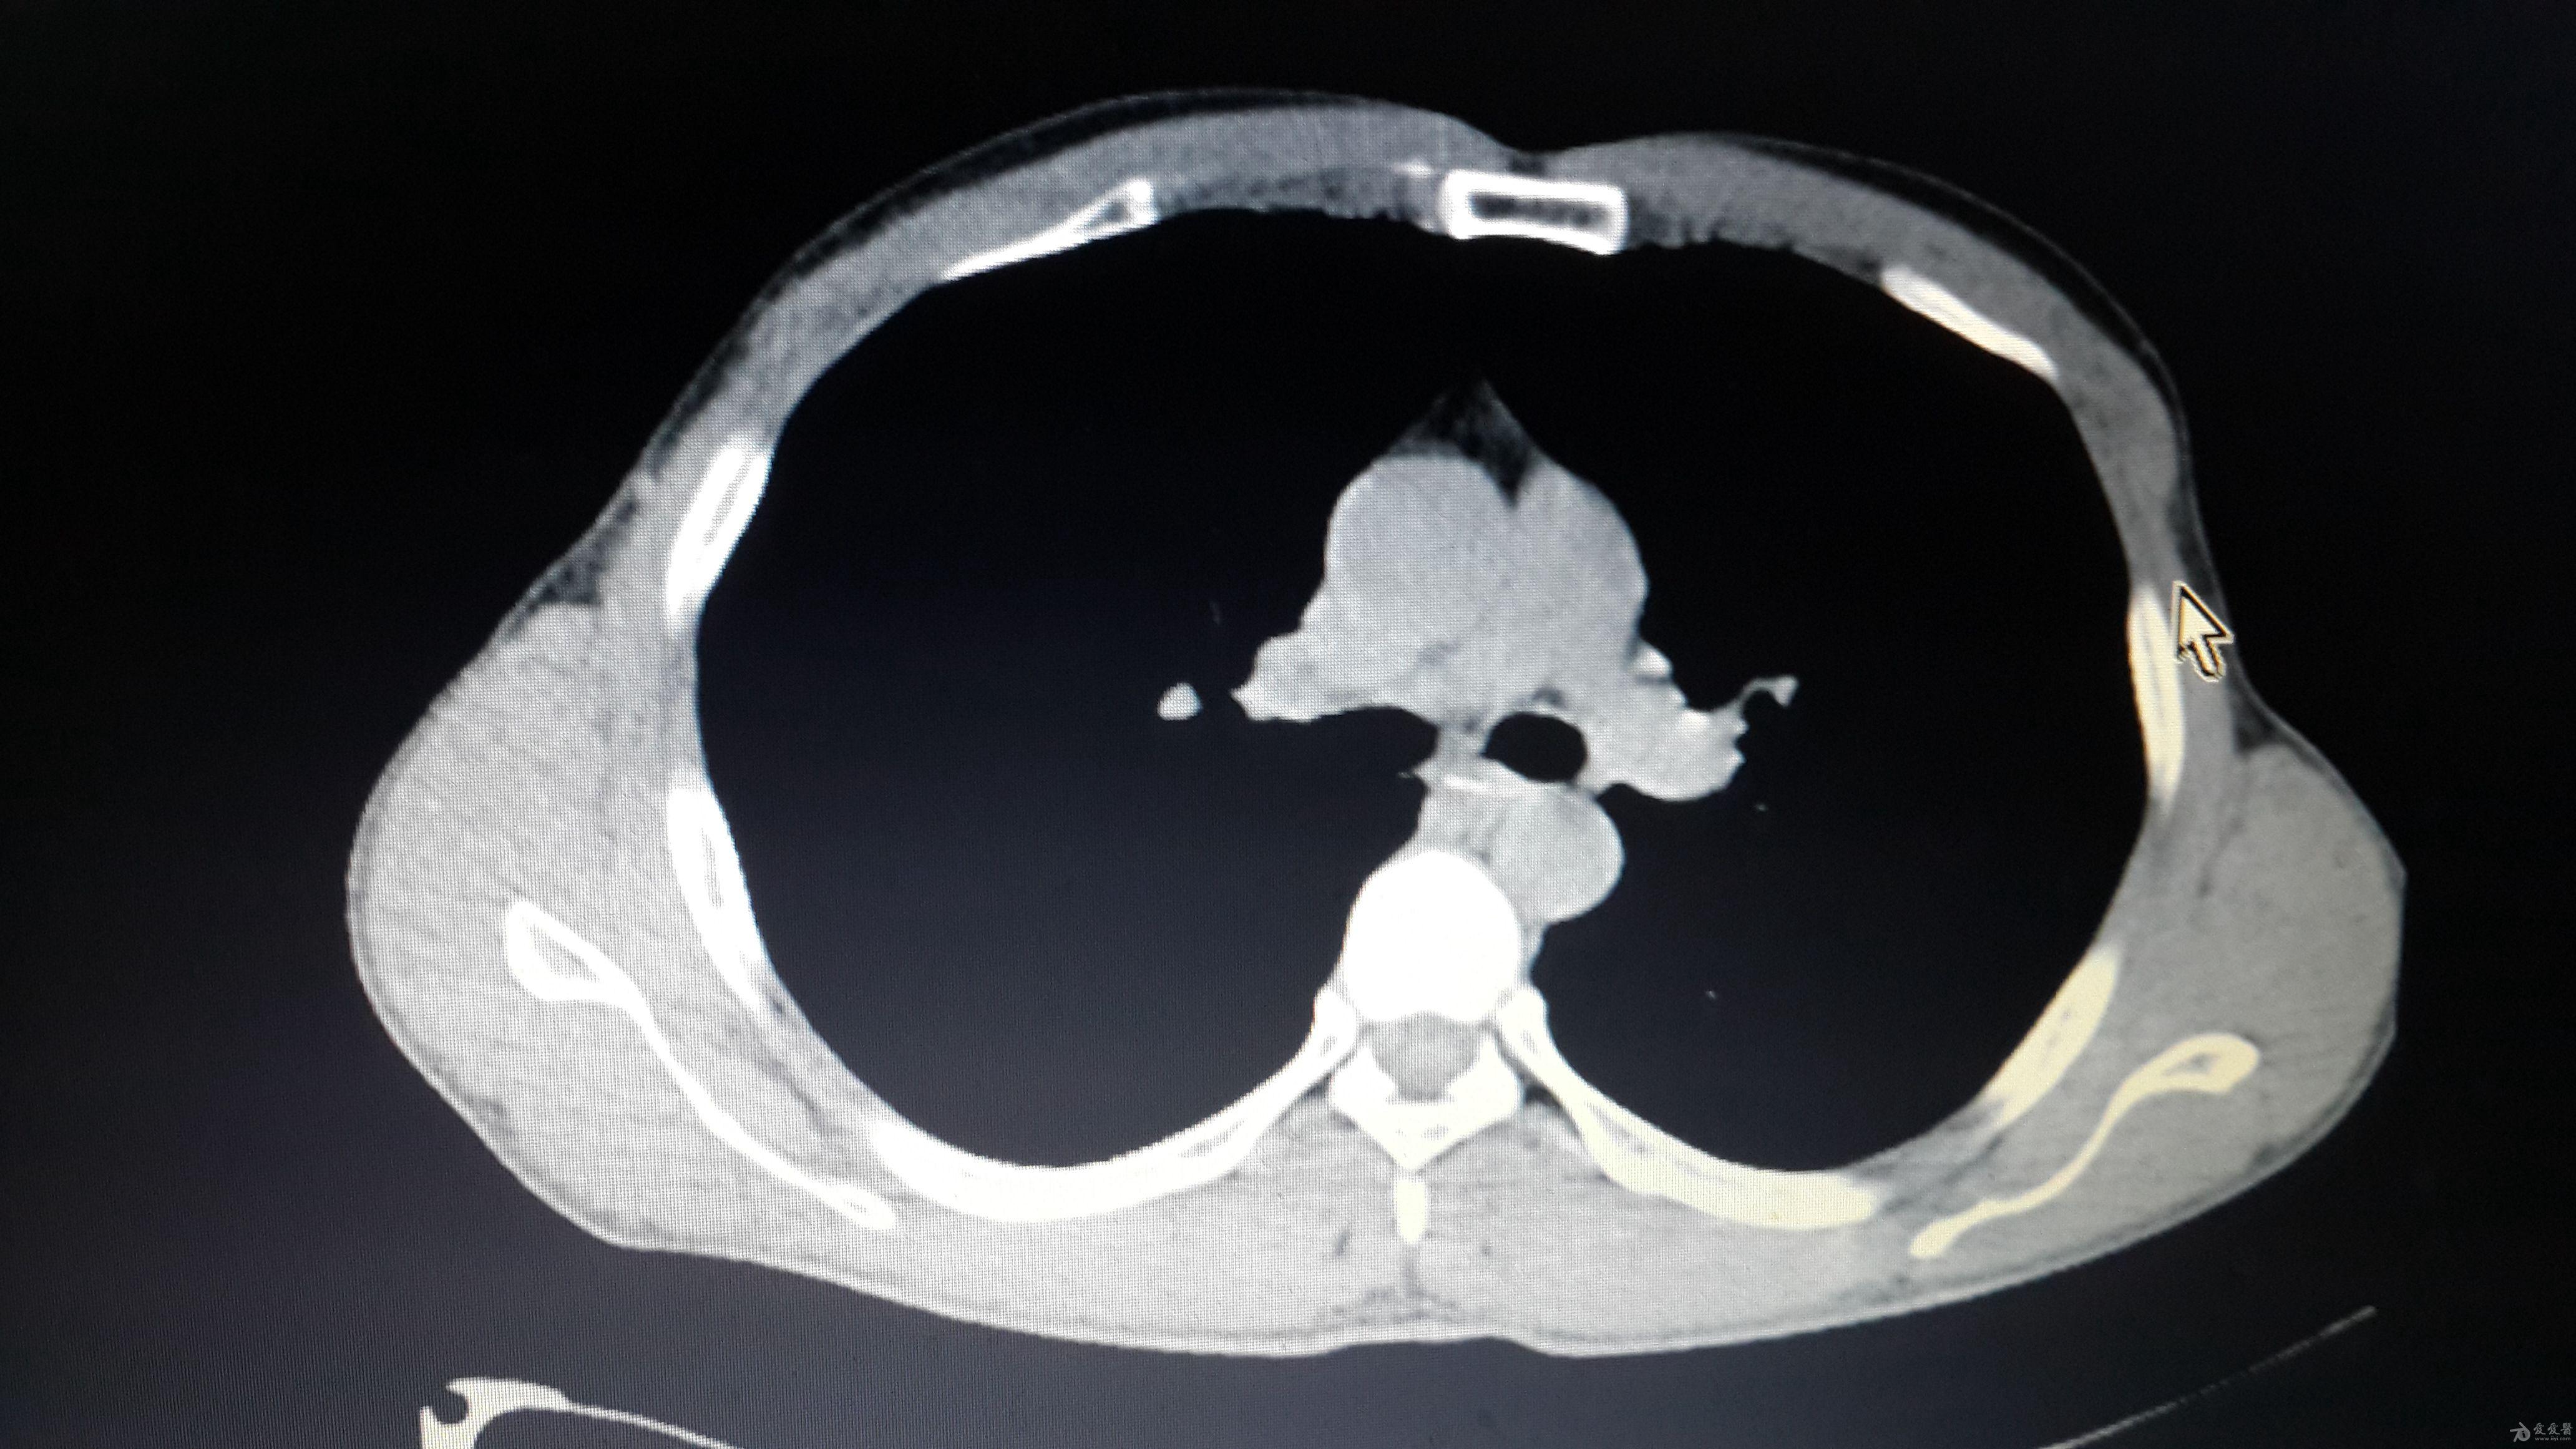

ct提示食管异物并纵膈脓肿形成

ct示:食管异物!